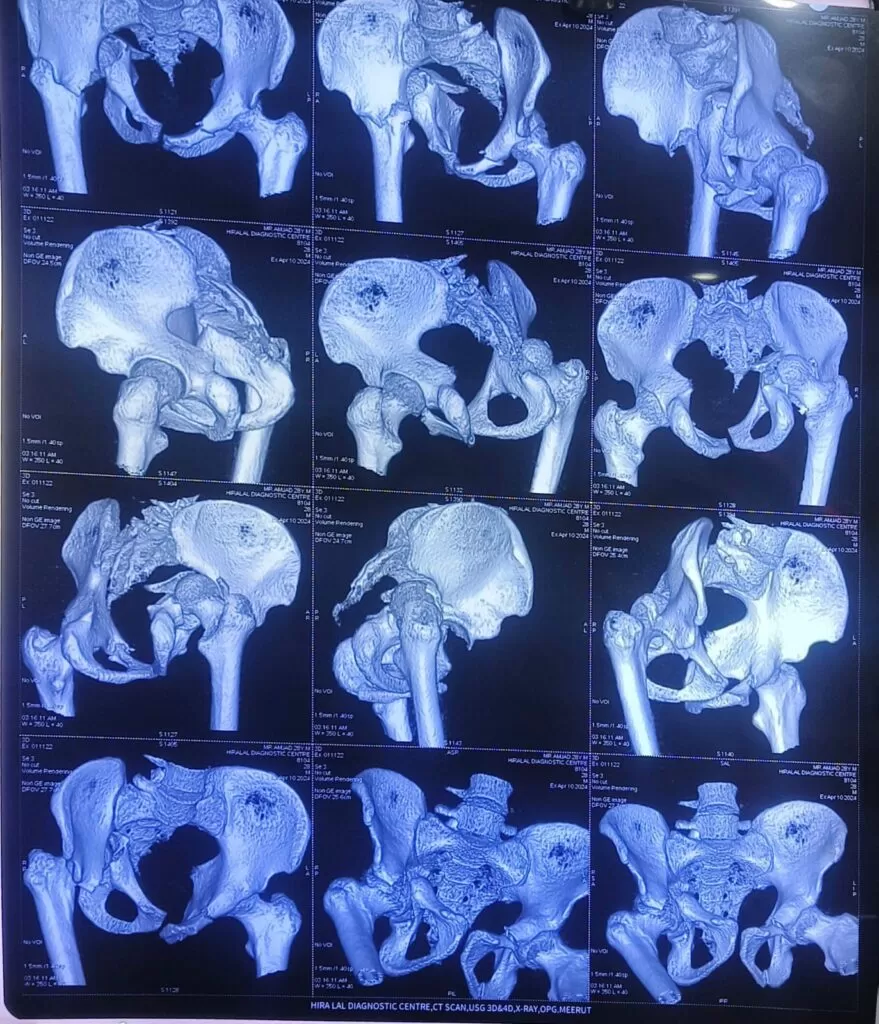

Mr. Amjad

Name: Mr. Amjad

Date of Operation: 12 Apr 2024

Age: 28 Years